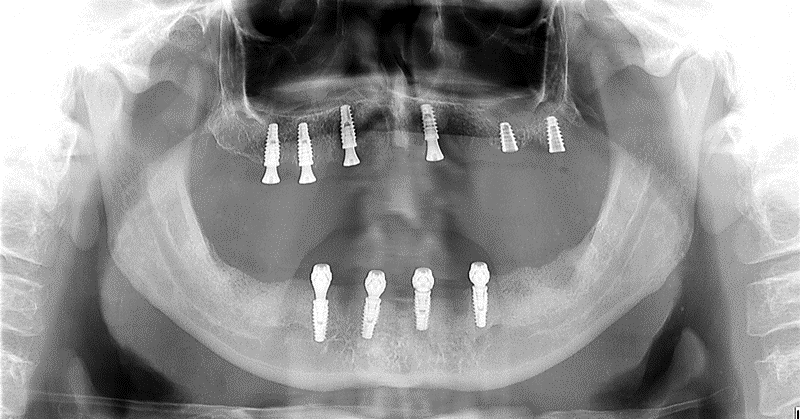

Paciente procurou tratamento protético reabilitador com queixa de dentes abalados e com mobilidade, mau hálito e sangramento gengival. Após exame clínico, radiográfico e tomográfico constatou-se a necessidade de exodontia de todos os dentes remanescente e instalação de implantes na maxila e mandíbula para posterior confecção de duas próteses do tipo Protocolo de Brånemark – prótese total fixa implantossuportada sobre implantes Maestro CM da Implacil De Bortoli, pilares do tipo mini-cônicos, barra metálica e prótese de resina acrílica, cuja abordagem encontra-se no dia a dia dos consultórios dentários.

Diante dos exames foi proposto ao paciente a extração de todos os dentes remanescentes, instalação de implantes na maxila e mandíbula e duas próteses totais provisórias durante o período de osseointegração.

Abaixo a descrição das etapas de confecção das próteses protocolos superior e inferior: